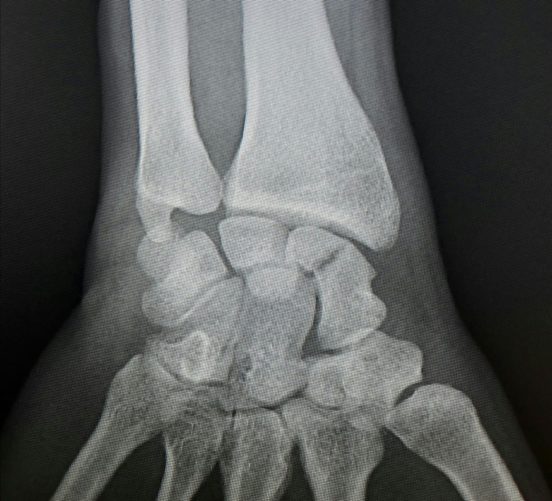

Fractura de escafoides para operar